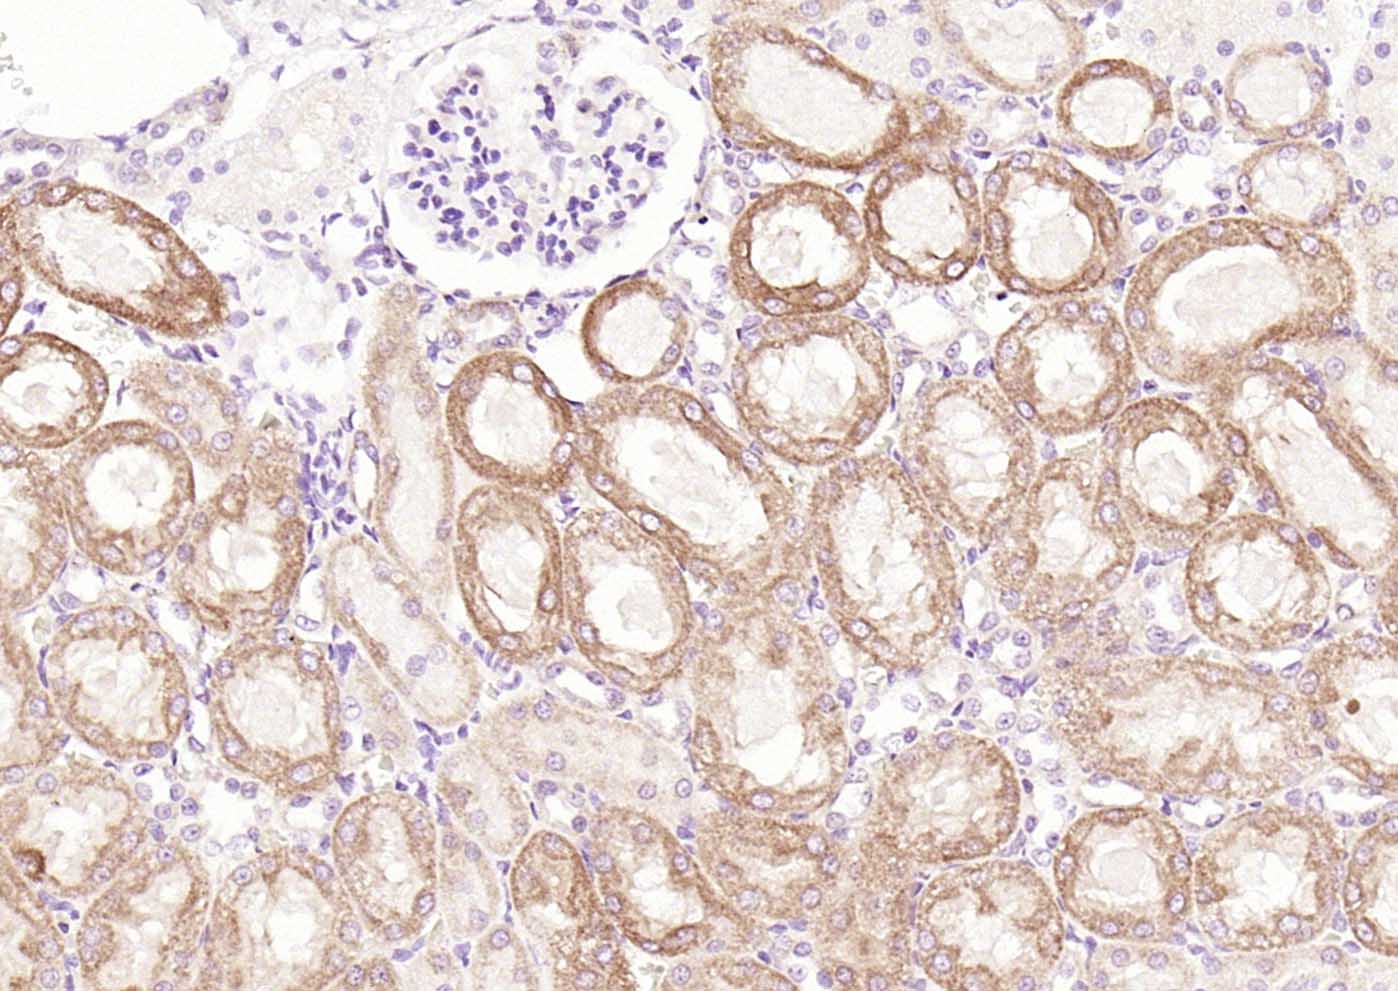

Paraformaldehyde-fixed, paraffin embedded (mouse kidney); Antigen retrieval by boiling in sodium citrate buffer (pH6.0) for 15min; Block endogenous peroxidase by 3% hydrogen peroxide for 20 minutes; Blocking buffer (normal goat serum) at 37°C for 30min; Incubation with (RelB) Polyclonal Antibody, Unconjugated (bs-3562R) at 1:200 overnight at 4°C, followed by operating according to SP Kit(Rabbit) (sp-0023) instructionsand DAB staining.